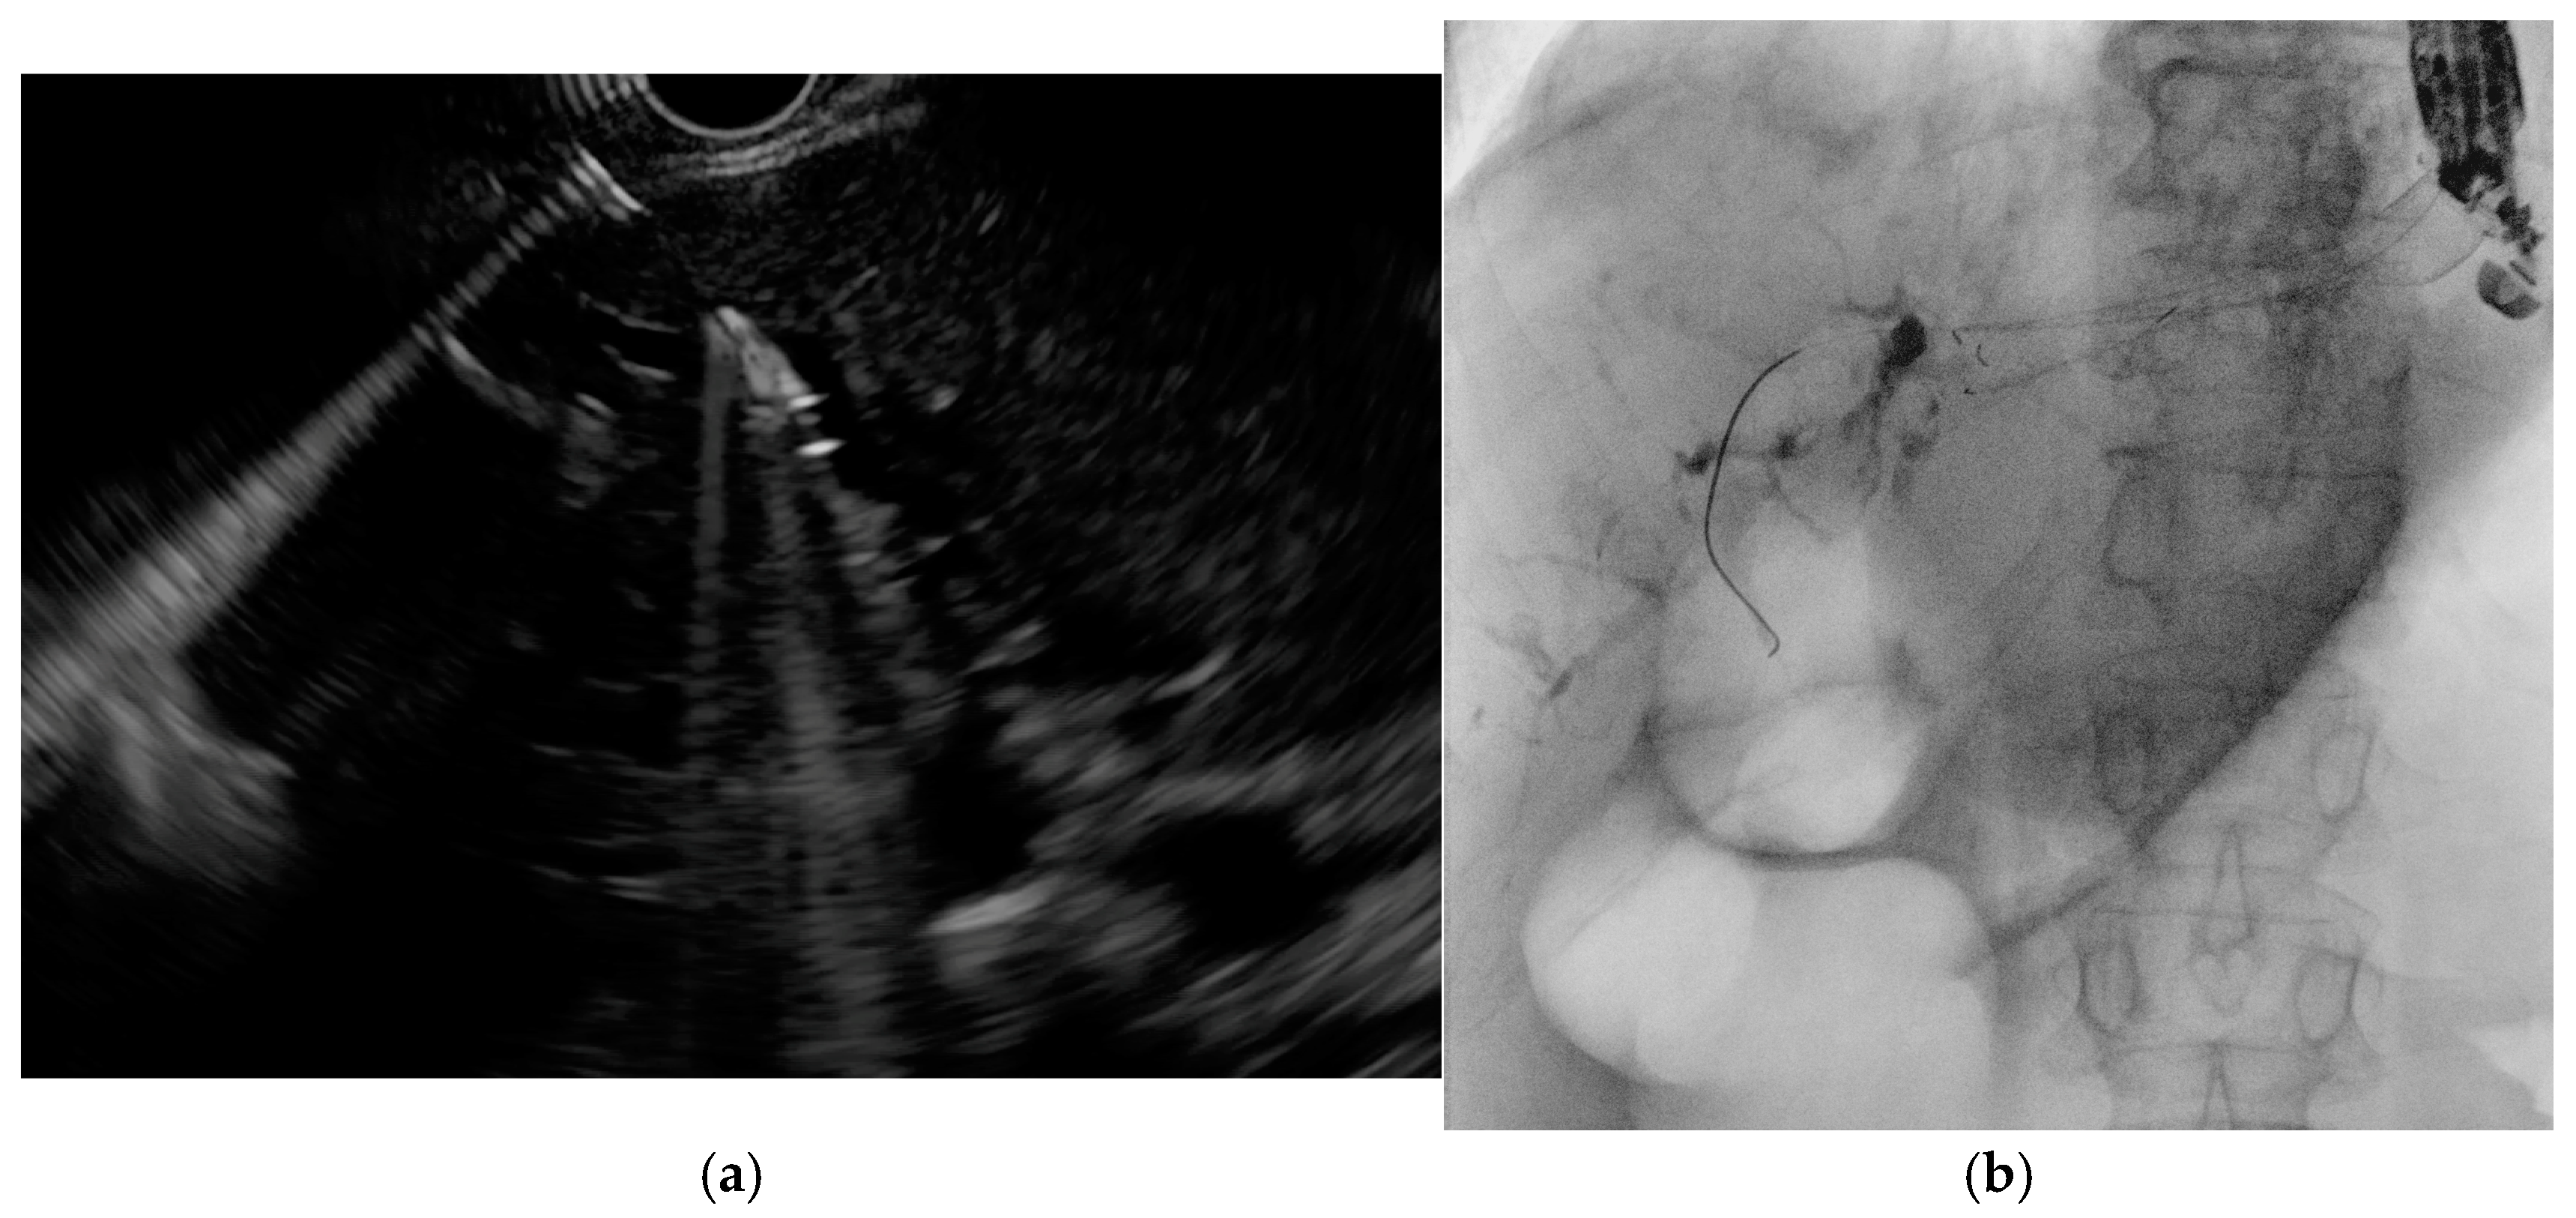

Figure 7. (a) EUS-guided puncture of intrahepatic bile duct with subsequent guidewire advancement; (b) placement of a self-expandable metal stent across the hepaticogastrostomy secured over the guidewire.

When ERCP fails or is not feasible (e.g., due to papillary tumor infiltration or surgically altered anatomy), EUS-guided biliary drainage (EUS-BD) represents a viable alternative. The main approaches include EUS–hepaticogastrostomy (EUS-HGS), rendezvous (EUS-Rv), and antegrade stenting (EUS-AG), each requiring specific guidewire strategies [34,35]. EUS-HGS typically involves puncturing the left intrahepatic bile duct from the stomach under EUS guidance (Figure 7a), followed by guidewire advancement, tract dilation, and stent placement (Figure 7b). A 19-gauge needle with a 0.025- or 0.035-inch guidewire is generally preferred for its stiffness and maneuverability [36], although a 22-gauge needle with a 0.018-inch wire may improve access to non-dilated ducts [37,38]. Devices compatible with 0.018-inch wires are now available [39,40], and in select cases, tract dilation may be avoided to reduce bile leakage risk [41]. Guidewire manipulation is often the most challenging step [42,43], particularly when an acute needle–duct angle (<85°) limits advancement [43], while obtuse angles (>135°) are associated with better outcomes [44]. Several rescue techniques have been described for failed guidewire passage, including exchanging the wire, liver impaction of the needle, use of an uneven catheter or balloon-assisted methods, and re-puncture of another duct [45]. Techniques such as the “moving-scope” or “jumping” methods have been reported to facilitate wire passage in difficult cases [46,47].